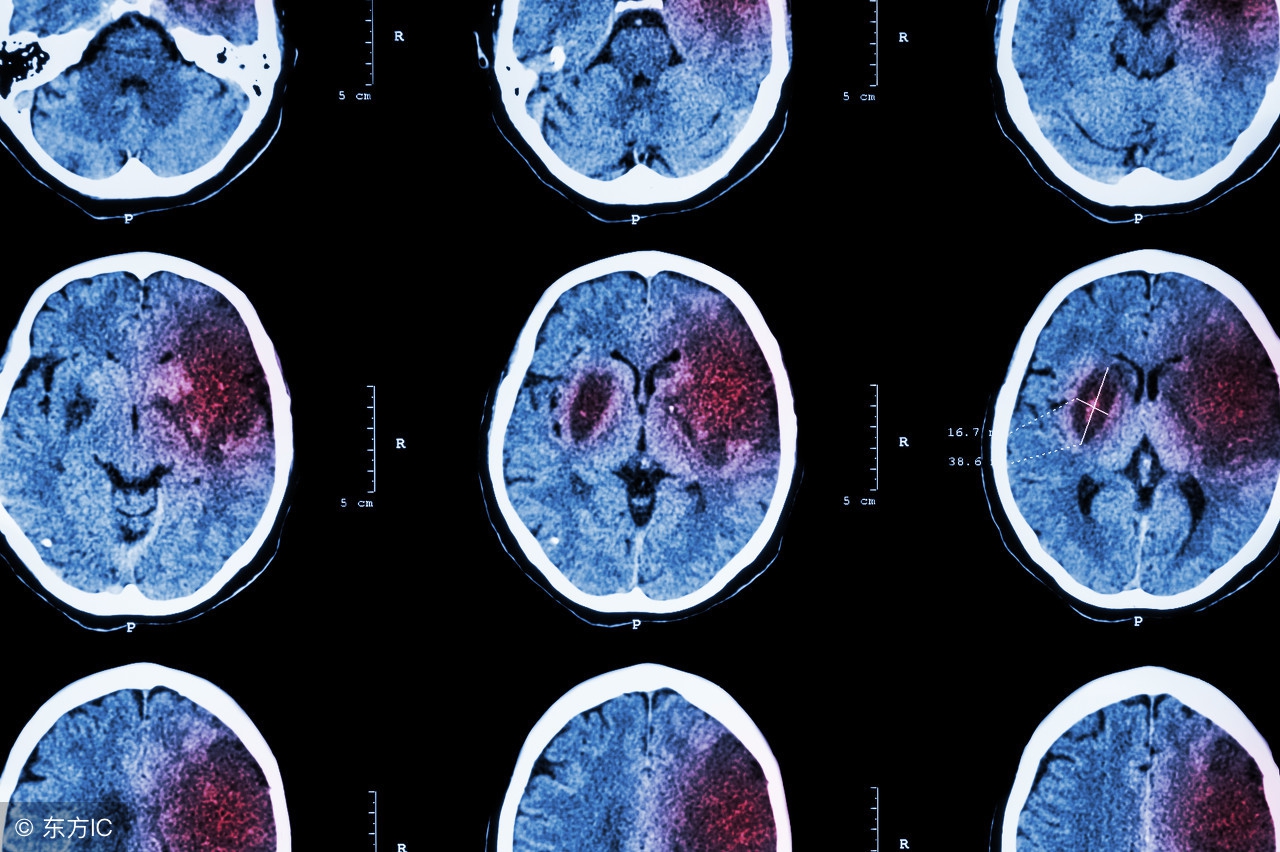

中风相信大家都知道,这是一种危害性非常大的疾病,可致使患者半身不遂、口舌歪斜等,所以对中风的多加了解和认识是非常有必要的。那么,不知道大家是否有听说过小中风,大家知道什么是小中风吗?小中风有什么症状呢?

小中风常在爆发性中风(主要中风)前的几个小时或几天内发生,医学上称这现象为中风预兆。小中风的医学名为暂时性缺血中风,是由于小血块阻塞血管而发生的,发作迅速。小中风发生前,通常会有明显的征兆。包括突然间口齿不清、说话模糊、身体局部麻痹、四肢无力、失去平衡力、老眼昏花、视力出现问题等等,这些症状可维持几分钟至数小时。发生小中风后,大部分患者会在一两个星期内发生大中风,如果能在小中风发生时及时治疗病情,病人的生命较有保障。